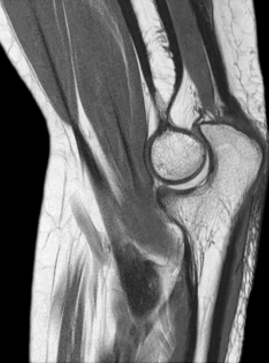

Sagittal:

![]() |